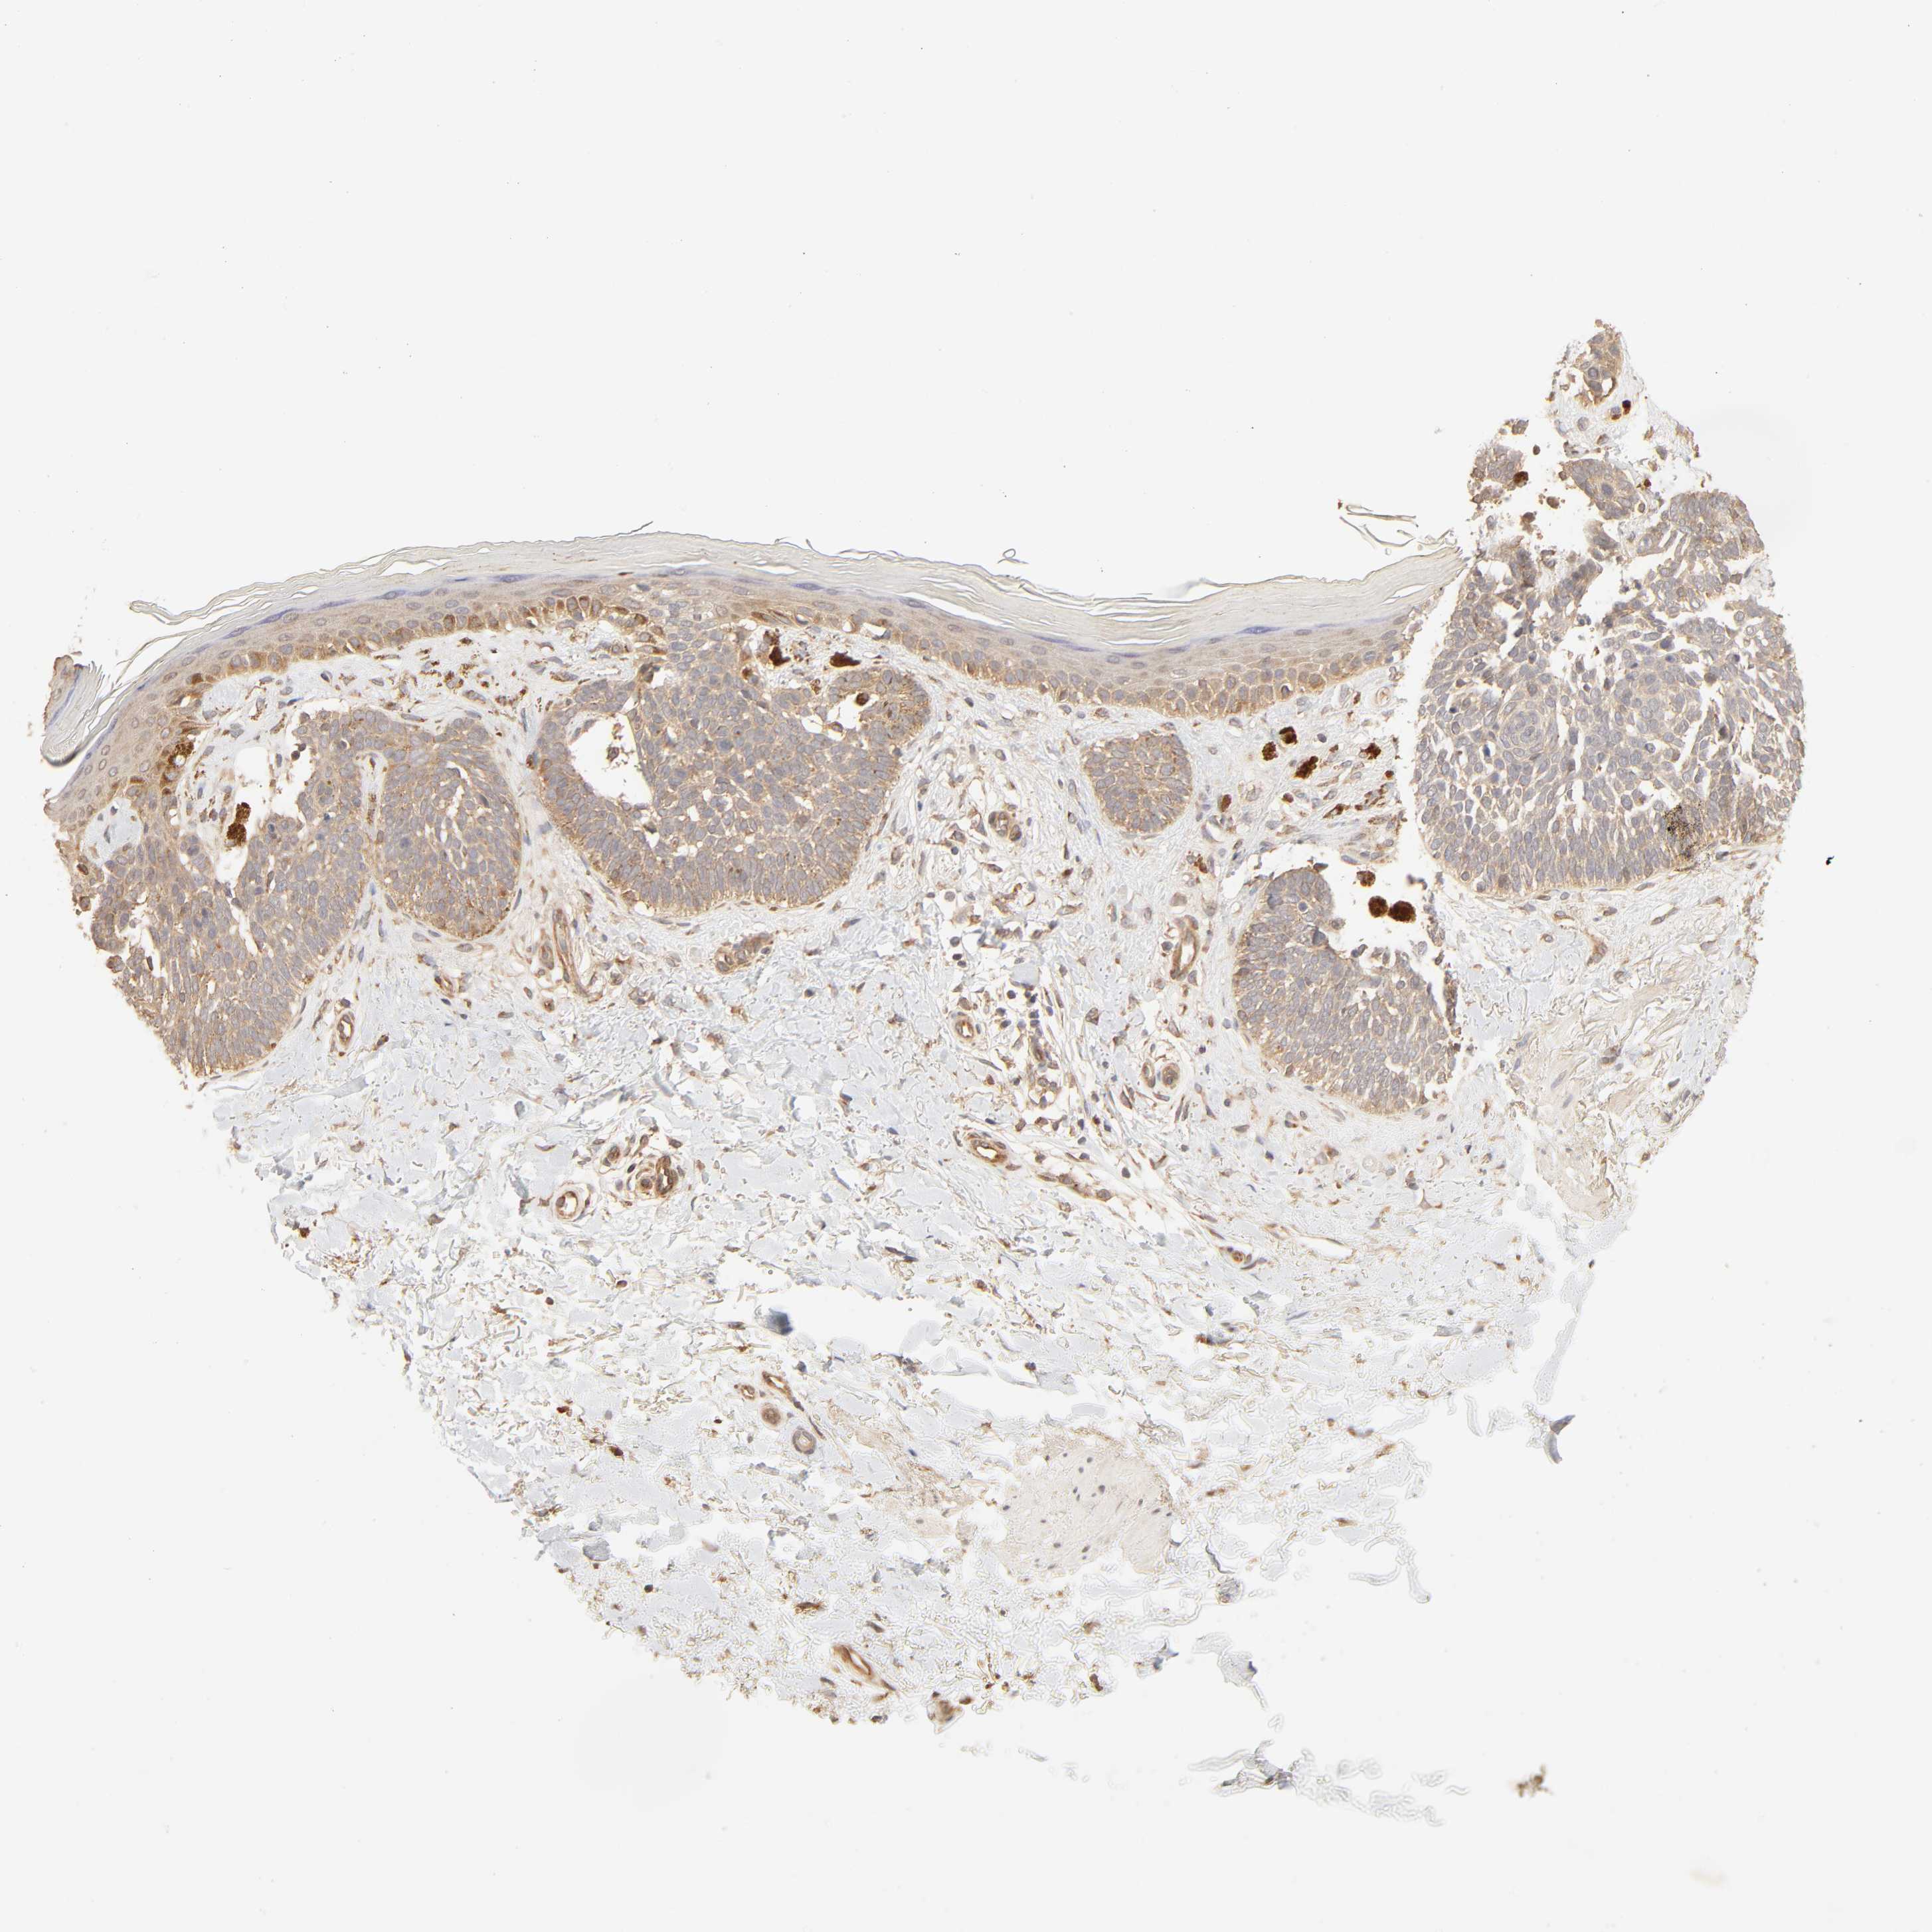

SKIN CANCER - Protein expressioni

A mouse-over function shows sample information and annotation data. Click on an image to view it in a full screen mode. Samples can be filtered based on level of antibody staining by selecting one or several of the following categories: high, medium, low and not detected. The assay and annotation is described here.

Antibody stainingi

Antibody staining in the annotated cell types in the current human tissue is reported as not detected, low, medium, or high, based on conventional immunohistochemistry profiling in selected tissues. This score is based on the combination of the staining intensity and fraction of stained cells.

Each image is clickable and will lead to virtual microscopy that enables deeper exploration of all samples and also displays staining intensity scores, fraction scores and subcellular localization as well as patient and tissue information for each sample.

Antibody HPA003897

Intensity

Strong

Moderate

Weak

Negative

Quantity

>75%

75%-25%

<25%

None

Location

Nuclear

Cytoplasmic/membranous

Cytoplasmic/membranous,nuclear

Squamous cell carcinoma, NOS

Basal cell carcinoma